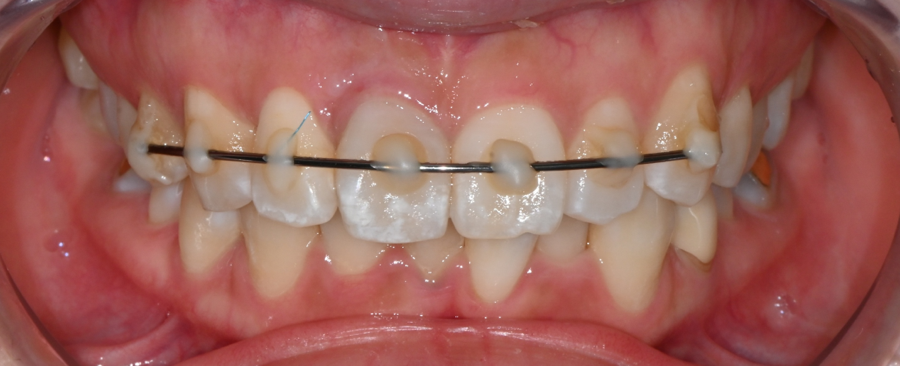

This is an X-ray of a patient who visited with a front tooth that had been completely knocked out due to the impact of a traffic accident.

This is a case in which temporary splint fixation using wire was first performed to stabilize the gums and surrounding structures supporting the teeth.